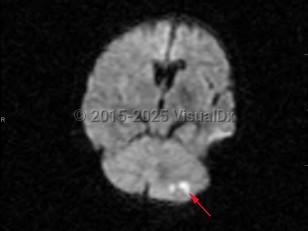

Risk factors for cerebellar strokes are the same as for other cerebrovascular pathologies: hypertension, hyperlipidemia, diabetes, cardioembolic risks such as atrial fibrillation, and tobacco abuse are chief among them. Cerebellar hemorrhages can also be caused by a rupture of vascular malformations; hereditary hemorrhagic telangiectasia (HHT) is a particular risk factor. Rupture of vascular malformations is a more likely cause in children. Other risk factors for cerebellar hemorrhages include sympathomimetic abuse such as cocaine use. Increased urinary sodium is associated with increased risk.